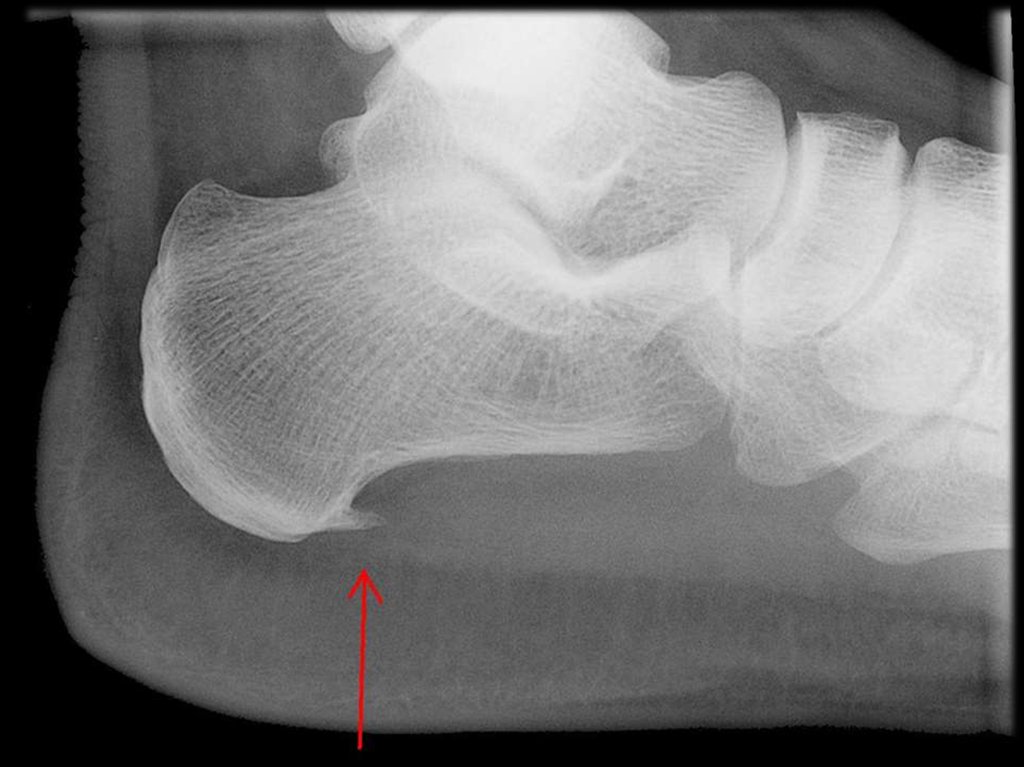

47. Плантарный фасциит («пяточная шпора»)

49.

50.